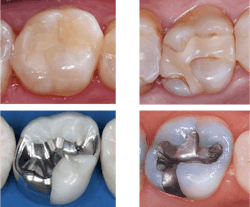

The digital images show only about 50% of the actual depth of small lesions. This often delays tooth restoration, causing unnecessary challenges with greater tooth destruction, more time and material used, wider exposure of restorations to occlusal wear, and potential pulpal damage (figure 2).

Sensors are about 9 mm thick and rigid. They cannot be adapted to the dental arch curvature, and they provide unequal radiation to the teeth and inaccurate identification of caries.

The cost of digital sensors is high and unjustified in the opinions of many dentists. Just like composites mentioned previously, dentists take radiographs many times per day. The manufacturer who overcomes these challenges will rapidly dominate the radiographic market. It is time for manufacturers to improve these inadequate diagnostic issues.